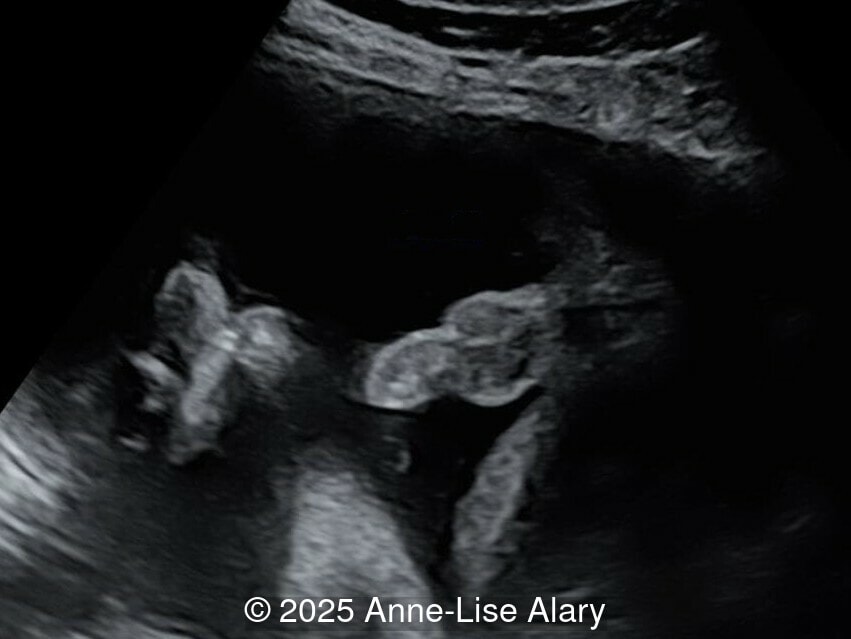

Our prenatal ultrasound revealed a male fetus with megabladder, dilation of both ureter and kidneys, and thinned kidney parenchyma consistent with Lower Urinary Tract Obstruction (LUTO). Additional findings suspected on ultrasound and confirmed on computed tomography included:

- Dysostosis: Hemivertebrae L3, fused L4-L5, abnormal left foot with short metatarsals and missing phalanges

The couple chose to deliver naturally. After prenatal needle aspiration of the bladder, the baby was delivered at 39 weeks gestation. Postnatal findings were consistent with Prune-Belly Syndrome with flaccid abdominal wall (similar to prune skin), lower urinary tract obstruction in a male fetus, imperforate anus requiring colostomy, lumbar hemivertebrae, and left foot hypoplasia including metatarsals and phalanges.